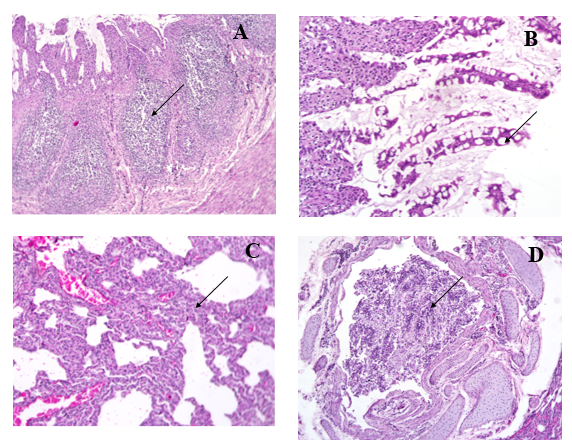

Hình 1. Bệnh tích đại thể của mèo mắc FPV

A – B: Ruột sung huyết, xuất huyết rải rác hoặc từng đoạn ngắn; C. Dạ dày sung huyết chứa nhiều dịch; D.Phổi viêm nhẹ.